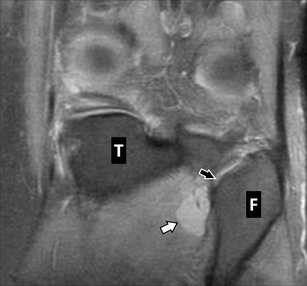

Baker cyst knee mri. A sports related injury or other blow to the knee can cause a bakers cyst. A bakers cyst also known as a popliteal cyst is a swelling that forms behind the knee when the tissue at the back of your knee fills with synovial fluid the lubricating fluid from the joint. A bakers cyst or a popliteal cyst occurs if there is an underlying intraarticular problem with the knee or and inflammatory reactions commonly as a result of losing bodies formed in conditions such as osteoarthritis rheumatoid arthritis gout acl tears meniscal tears or because of particles following knee arthroplasty mostly from the.

They represent neither a true bursa nor a true cyst as they occur as a communication between the posterior. Baker cysts or popliteal cysts are fluid filled distended synovial lined lesions arising in the popliteal fossa between the medial head of the gastrocnemius and the semimembranosus tendons via a communication with the knee jointthey are usually located at or below the joint line. Knee cyst is a fluid filled synovial fluid swelling that causes a lump around the knee area.

Miscellaneous cyst like lesions may require a more dedicated mr protocol for a correct diagnosis. This type of arthritis which results from the buildup of uric acid in the blood can lead to a bakers cyst. The ganglion knee cyst can cause tightness and restricted movement hence it can be painful when you bend or extend your knee.

The pain can get worse when you fully flex or extend your knee or when youre active. This makes it swollen and inflamed. Synovial cysts meniscal cysts normal knee bursae and recesses have characteristic mr appearances.

Cystic lesions are common in knee mri and the commonest the bakers cyst has an incidence of 38. If the cyst breaks open pain may significantly increase with swelling of the calf. Cysts can vary in size and can very occasionally develop.